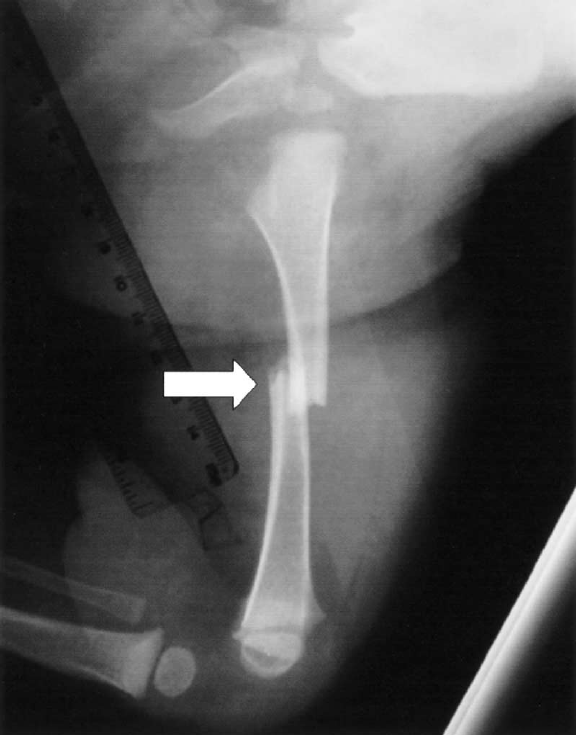

Impacted Fracture - एखादे हाड तुटते तेव्हा त्या हाडाचा हिस्सा दुसऱ्या हाडांमध्ये घुसण्याची स्थिती.

Pathological Fracture - आजारामुळे हाडे कमजोर होऊन तुटणे.